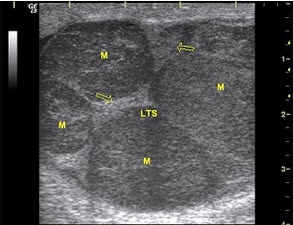

29、单项选择题

某患者阴囊部疼痛不适,超声声像图如下,最可能的诊断为()

A.附睾炎

B.睾丸炎

C.睾丸肿瘤

D.附睾结核

E.附睾肿瘤